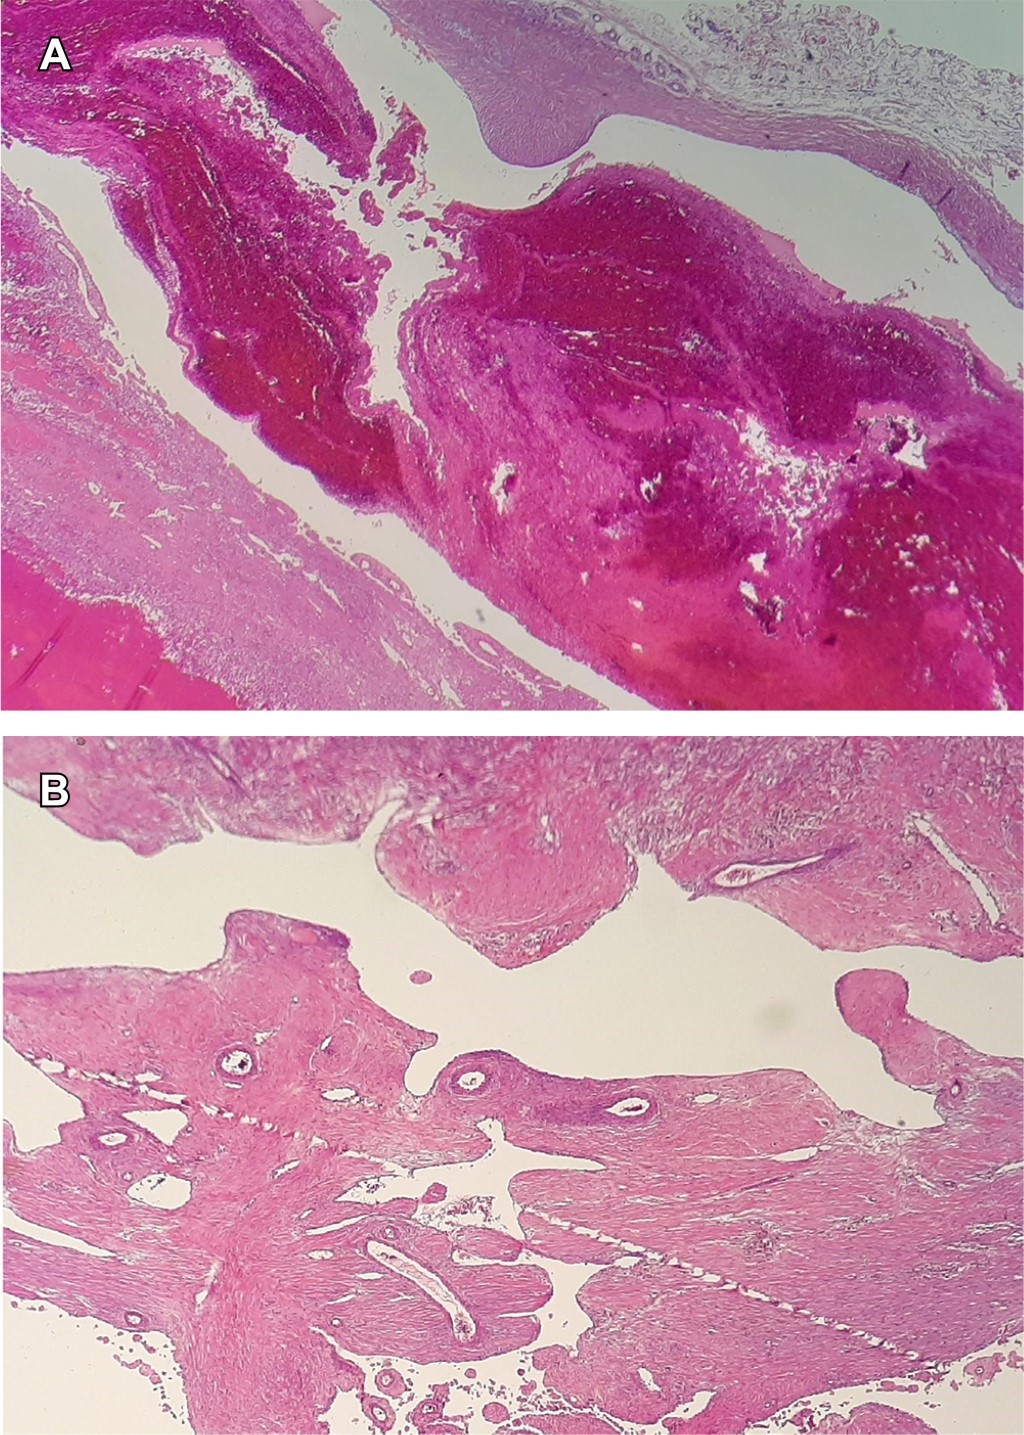

En la exploración quirúrgica se observó masa de coloración violácea con adhesiones laxas al nervio cubital y a la arteria cubital. Se ligó el cuello dependiente de la arteria, sin necesidad de resecar un segmento de la arteria o nervio cubital. El estudio histológico reportó pseudoaneurisma sacular trombosado con hiperplasia endotelial (Figura 3).

Figura 3